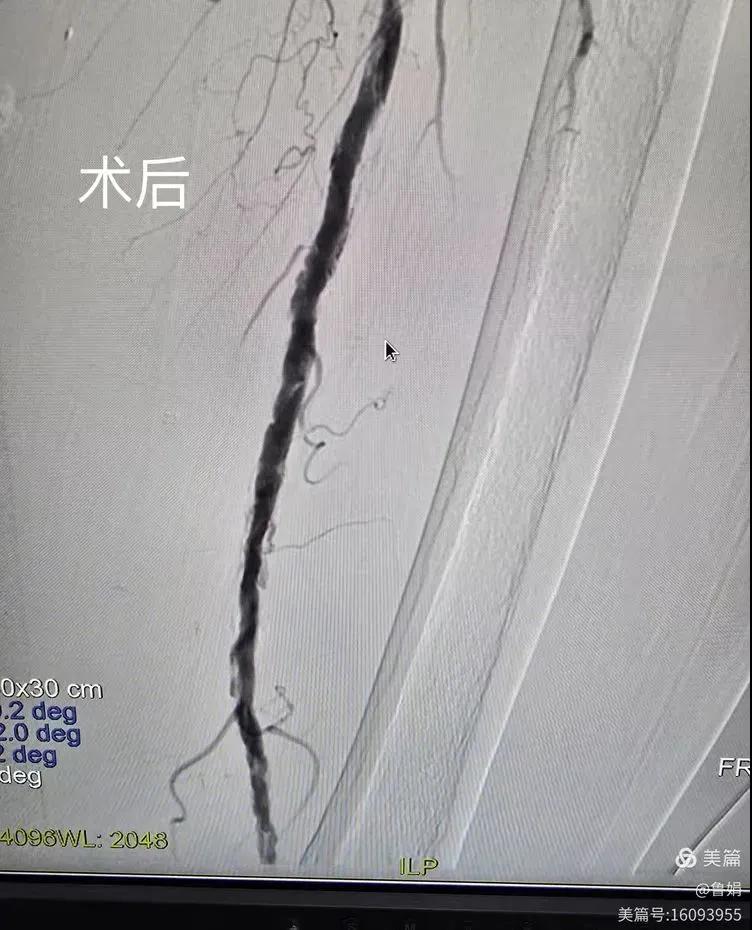

據(jù)悉,該患者,女,73歲,下肢動(dòng)脈硬化閉塞癥,“以靜息痛,間歇性跛行”入院,CTA評(píng)估:股淺動(dòng)脈,腘動(dòng)脈間斷性多段重度狹窄,外二科血管外科團(tuán)隊(duì)根據(jù)患者病情,結(jié)合檢查結(jié)果,經(jīng)過科室會(huì)診后,決定對(duì)該病人行介入治療。手術(shù)由周創(chuàng)業(yè)副主任與北大一院血管外科專家郭宏杰教授聯(lián)合開展,對(duì)股淺動(dòng)脈,腘動(dòng)脈重度閉塞段行血管開通+藥涂球囊擴(kuò)張成形,術(shù)后狹窄明顯緩解,血流恢復(fù)!

患者術(shù)后感受良好,表示原本困擾多年左腿疼痛與麻木、冰涼的癥狀較前好轉(zhuǎn),甚至消失,取而代之的是一種久違的溫暖與輕松,并對(duì)外二科血管外科團(tuán)隊(duì)的精湛技術(shù)表示肯定和感謝。